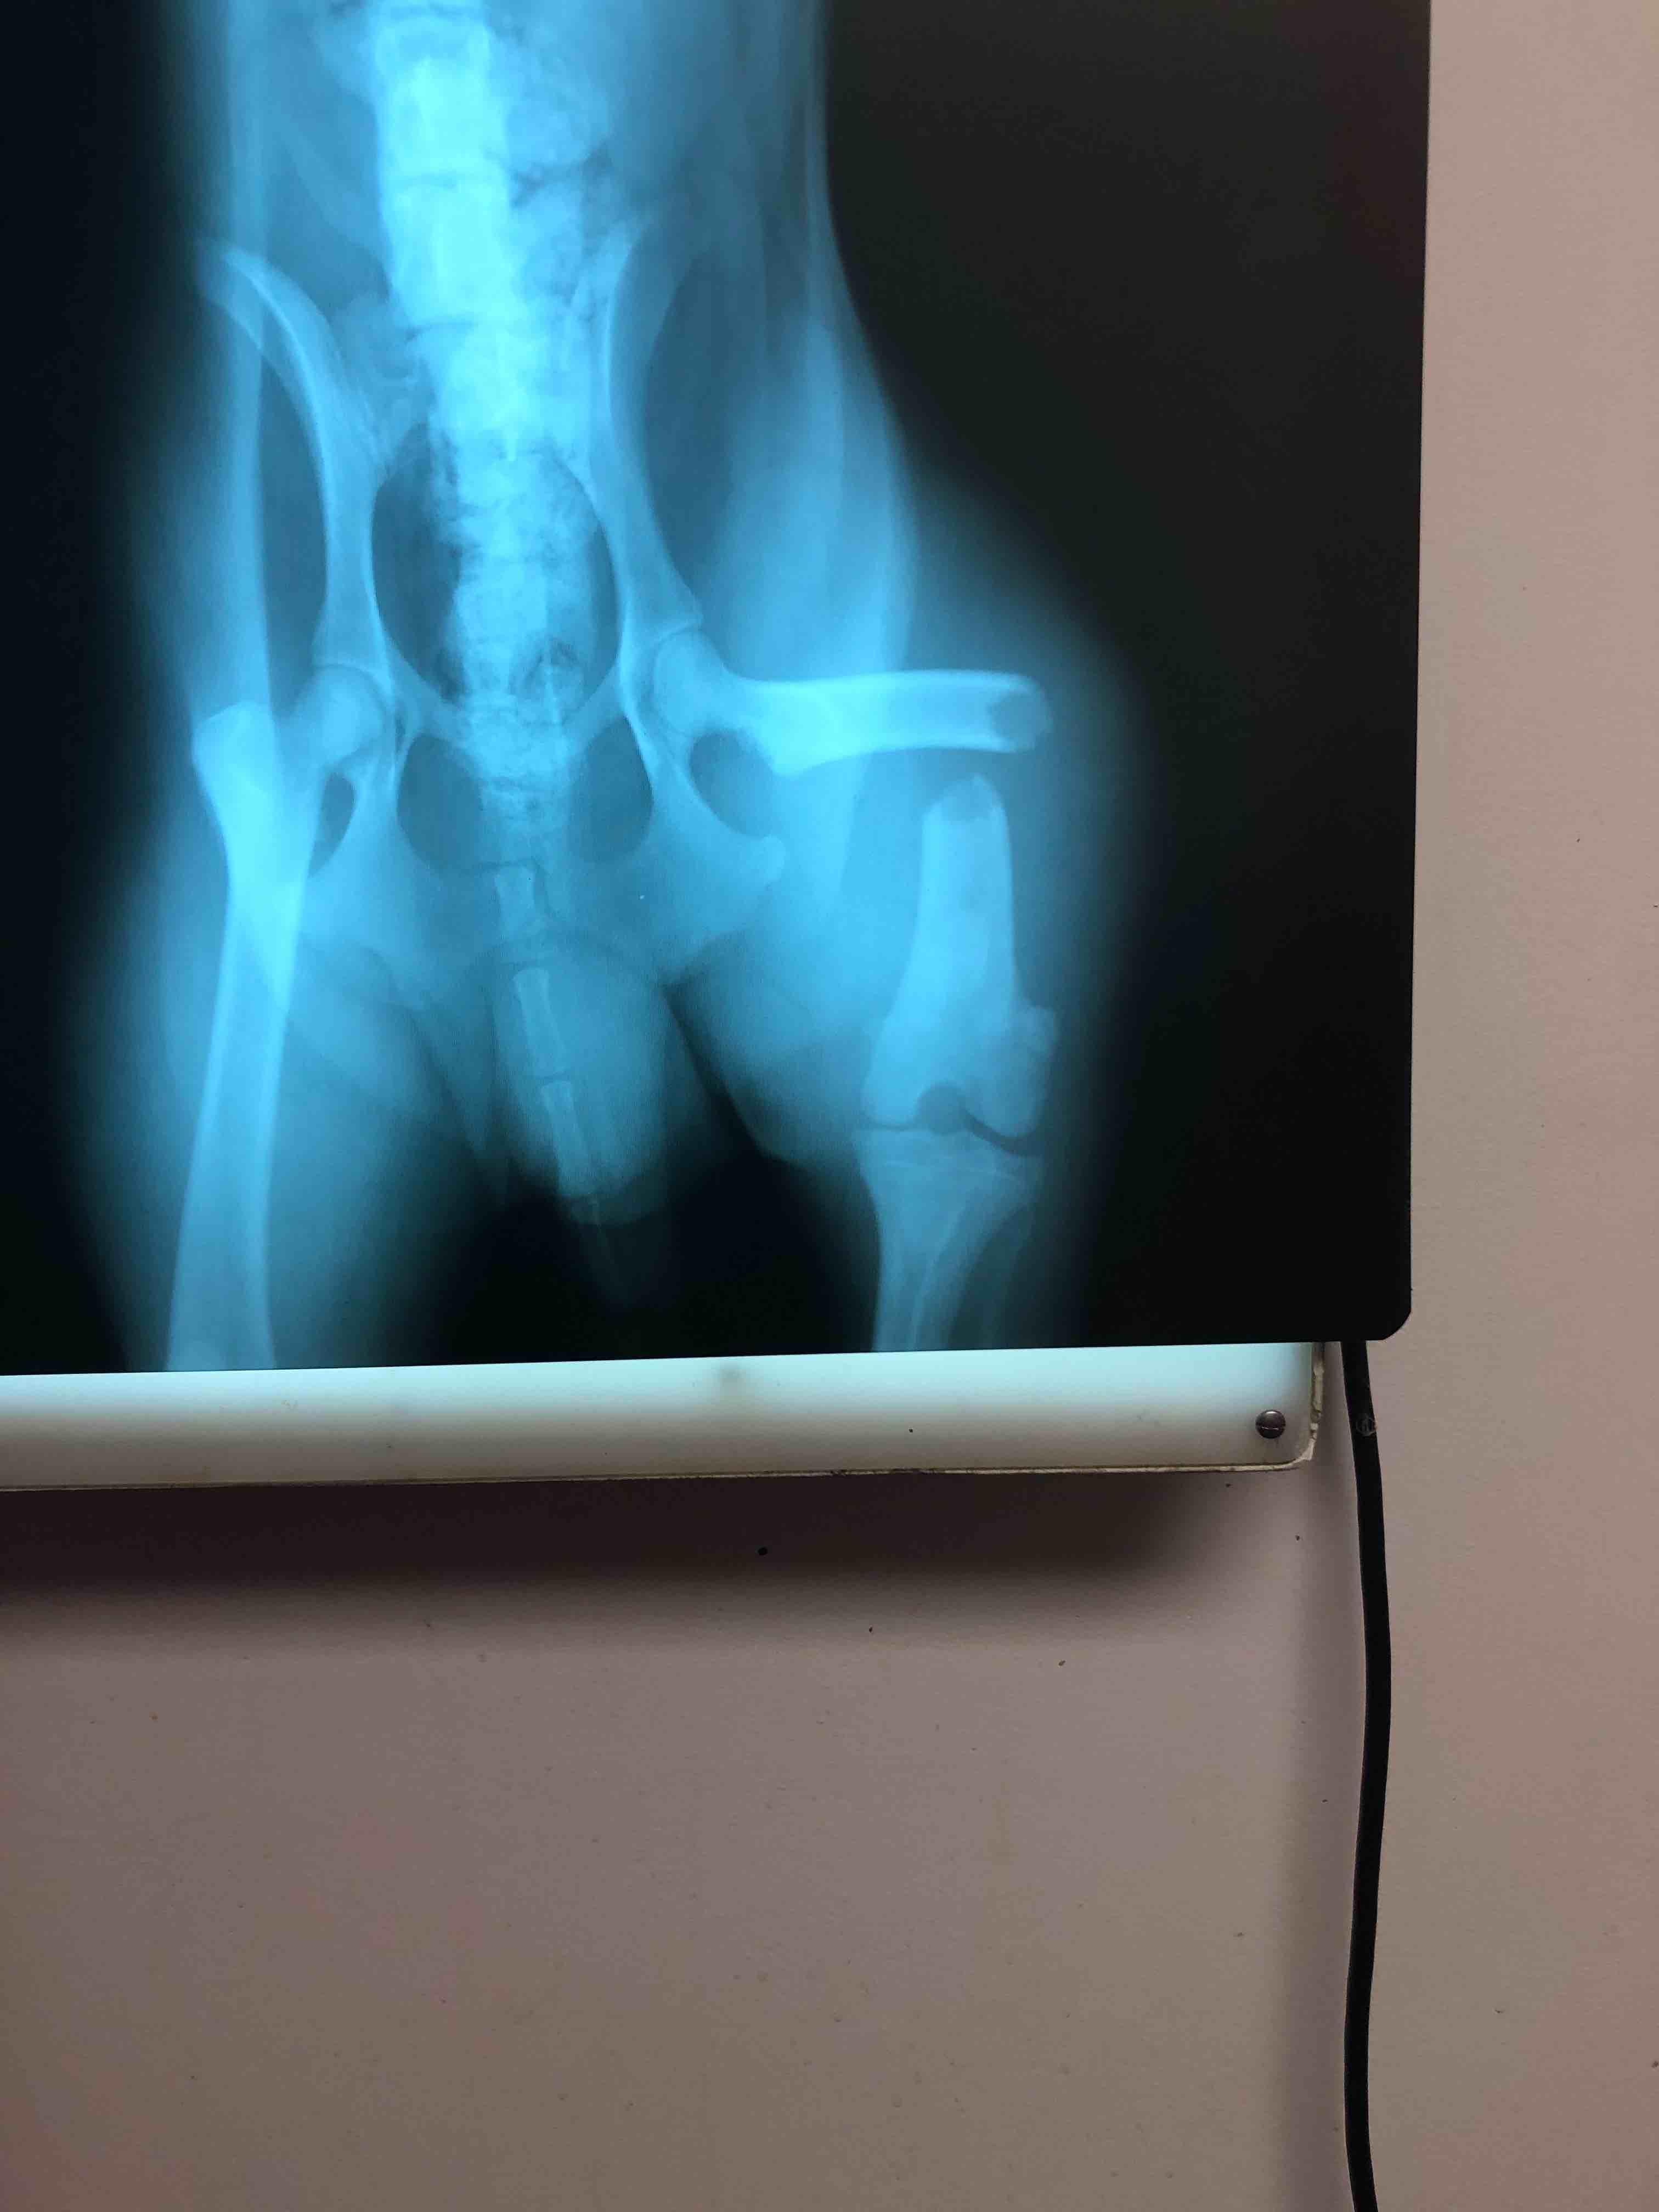

My dog was ran over by a car about a year ago and he had surgery on his leg. The put a rod on the inside of his leg to help the bone grow back together but they never took it out and I’m afraid that he might get an infection or something. The rod has been in there for a while. What do I need to do? I attached pictures of the X-Ray and a picture of my dog. He’s bigger now.

Thanks for using Petco Pet Education Center, formerly Petcoach! In general, pins and plates can safely be left in the body indefinitely. There is always a small risk of infection, in which case the pin/plate would be removed. The risk of infection will be present life-long but is less than 5%. If you are worried about it, head into the vet for an x-ray and to discuss if it is worth taking out. (A pin that exits near the surface of the skin can sometimes be removed quickly under sedation.) Best of luck to you and Rocky!